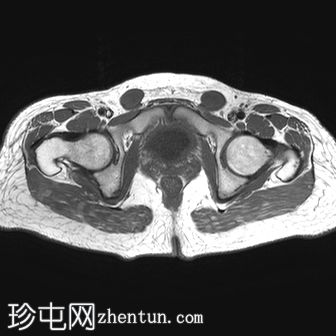

轴位

T1加权像

轴位T1加权像

脂肪抑制

子宫缺失

卵巢缺失

阴道下三分之一发育不全,上三分之二缺失

可见双侧腹股沟卵圆形结构,提示隐睾(右侧约2.4×2厘米,左侧约2.3×2厘米)

上述特征符合雄激素不敏感综合征(睾丸女性化综合征)的典型表现。

核型分析显示46XY染色体。